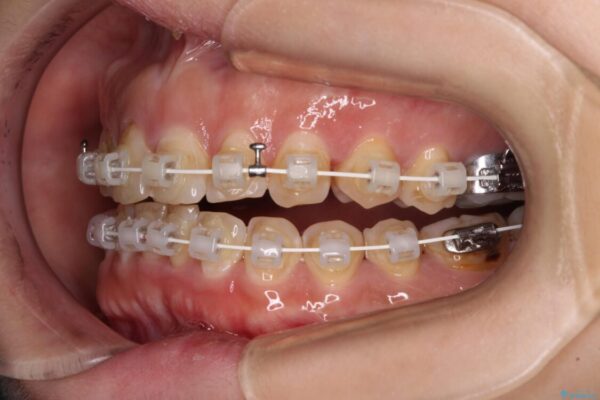

矯正装置

審美装置

なるべく早めに治療を終えたいとのことで、補助装置を用いて上顎臼歯を後方に移動させ、同時にワイヤー装置にて整えることとしました。

治療途中

• 【モニター】飛び出た前歯を整えたい ワイヤー矯正治療 治療途中画像